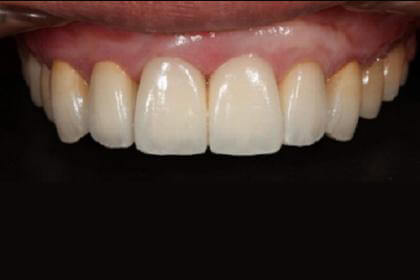

Before

総合的な審美治療

After

基礎データ 30代女性

治療期間 2003〜2009年

治療費 144万(矯正治療の費用は他院にて請求)

主な治療 歯列矯正・抜歯・軟組織移植・クラウンブリッジ補綴

治療計画 不正なクラウンを除去、保存できない歯を抜歯し、正しい噛み合わせを作れるように外科矯正を含んだ矯正治療を行う。

矯正治療後、前歯部の吸収した組織を増大し、クラウンブリッジを作成した。